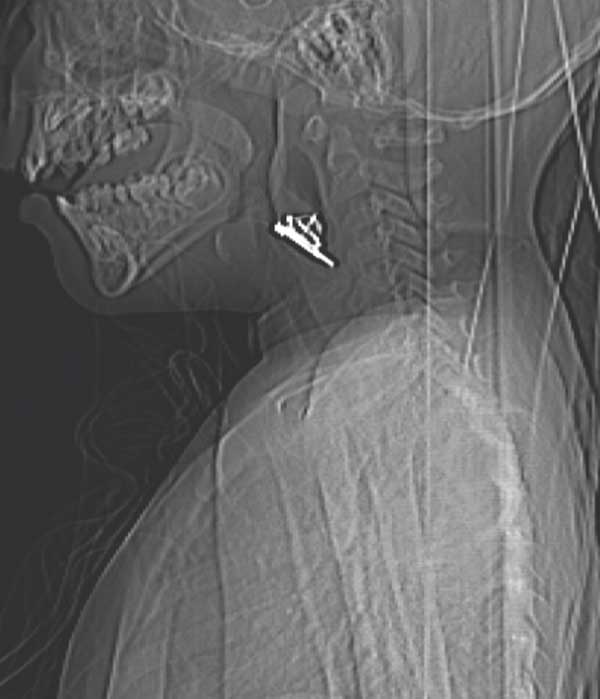

C. � un bambino di 2 anni, giunge in Pronto Soccorso con una storia, incominciata 7 giorni prima, di faringodinia insorta improvvisamente, associata a febbre (38,5 �C) difficilmente controllabile con l�antipiretico, disfagia, scialorrea e dolore al collo. Conside rata tale clinica, si era deciso di ricoverare il bambino presso la divisione pediatrica di riferimento. L�esame obiettivo aveva mostrato la presenza di torcicollo con flessione del capo verso destra, in posizione antalgica. Gli esami di laboratorio avevano evidenziato una leucocitosi neutrofila (GB 22440 di cui 19300 neutrofili) e una Proteina C-Reattiva elevata (13 mg/dl). C. era stato sottoposto a una visita ORL che non aveva mostrato elementi significativi. Nel frattempo era stata avviata empiricamente la terapia antibiotica con ceftriaxone endoven a (1,3 g) che aveva portato a un netto miglioramento della sintomatologia gi� dopo 24 ore: il bambino si era sfebbrato, non aveva lamentato pi� dolore al collo n� disfagia e gli indici di flogosi si erano negativizzati. Tuttavia, al quinto giorno dall�inizio della terapia antibiotica, il piccolo presenta nuovamente dolore al collo, disfagia e scialorrea, sebbene persista apiressia e non ci sia un rialzo degli indici di flogosi. Con questa storia si decide il trasferimento presso il nostro Istituto. Al suo arrivo si presenta in buone condizioni generali ma molto sofferente. L�esame obiettivo e l�endoscopia non evidenziano alcun elemento di rilievo. Nel sospetto di un ascesso retrofaringeo, viene eseguita la TC (Figure 1 e 2).

Figura 1. TC in sezione coronale. | Figura 2. TC in sezione sagittale.

La TC rimane dunque il Gold Standard per la diagnosi che �

stata fondamentale anche per evidenziare la presenza del corpo

estraneo.